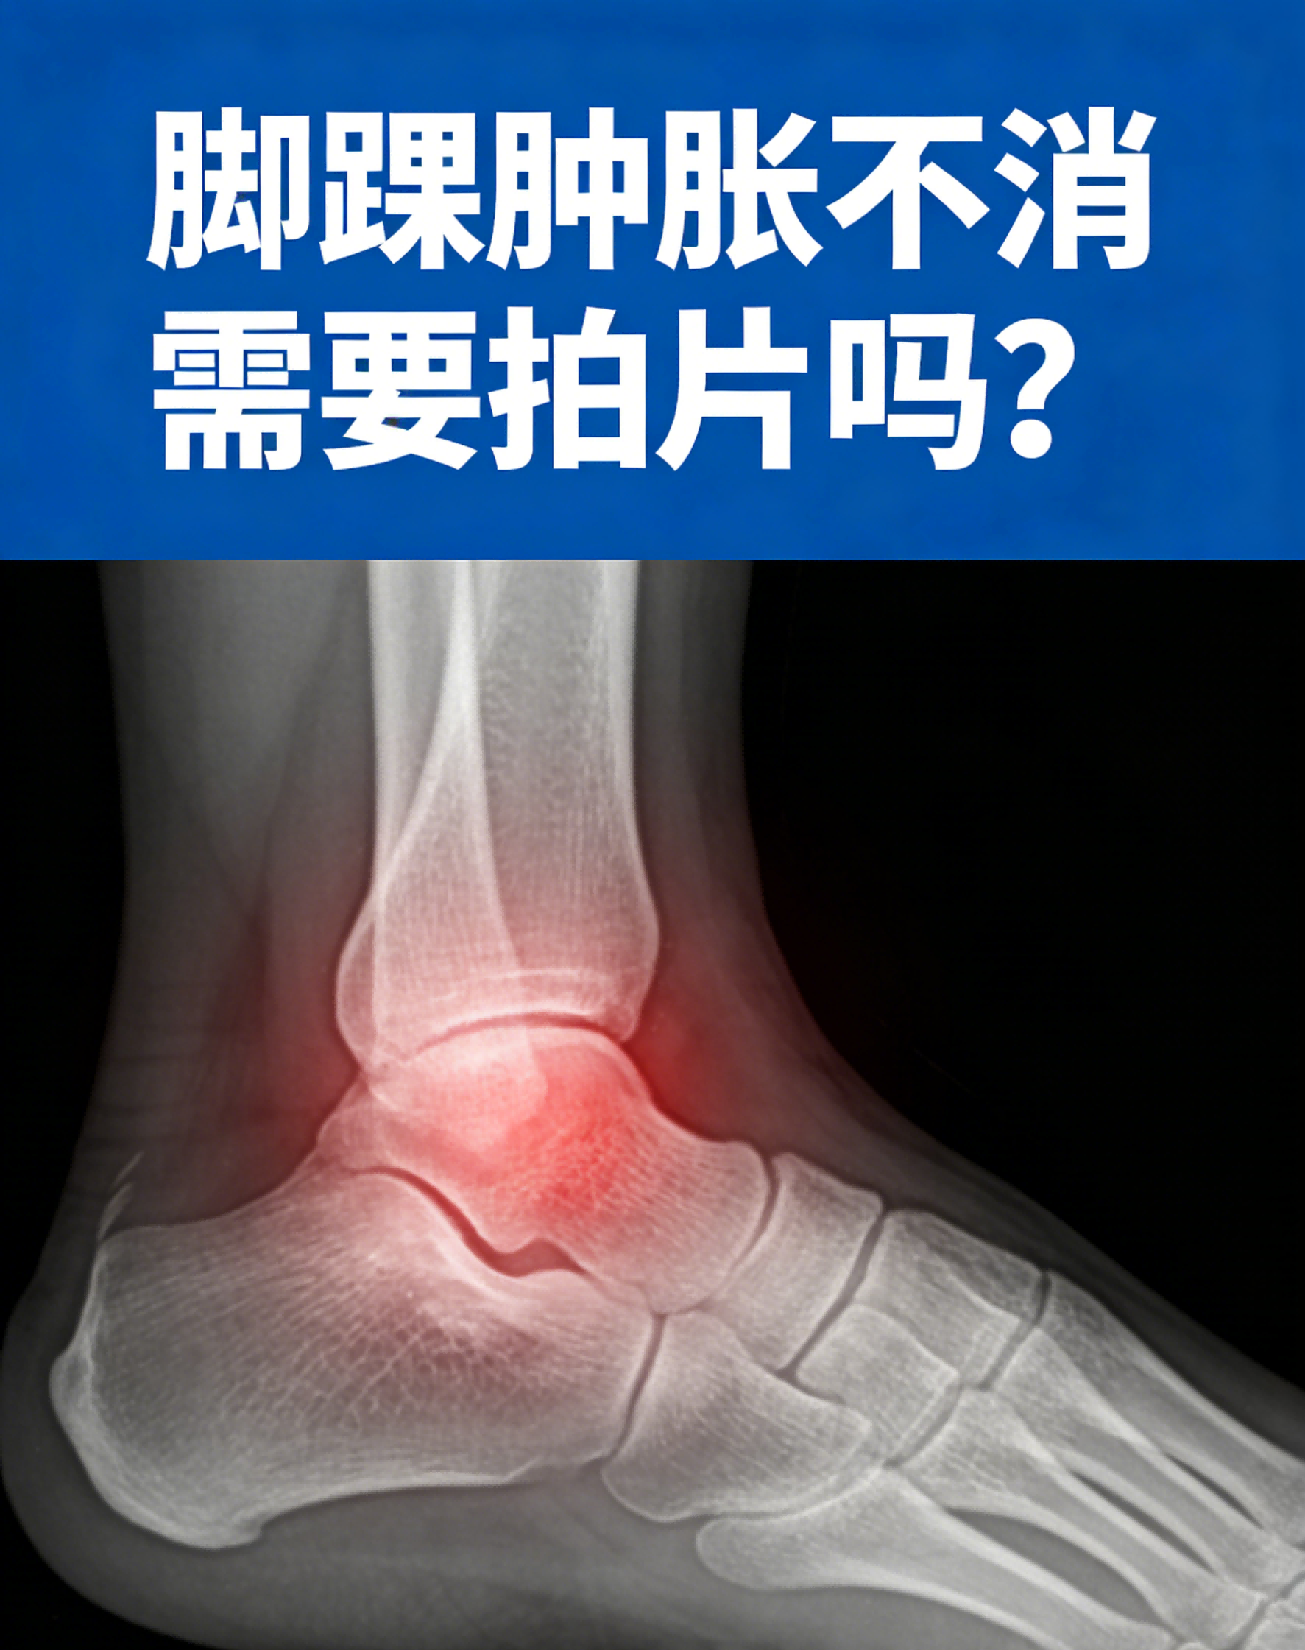

脚踝肿胀不消需要拍片吗?

脚踝肿胀不消是否需要拍片,需结合肿胀时长、伴随症状综合判断,不能一概而论,核心是排查骨骼、关节是否受损。若肿胀是轻微扭伤、劳损导致,仅轻微肿胀、无剧烈疼痛,活动不受限,且肿胀在3-5天内逐渐消退,可暂时不拍片,通过休息、冷敷、抬高患肢缓解即可。

若肿胀持续超过1周不消,或伴随剧烈疼痛、脚踝畸形、活动受限,甚至按压时有骨摩擦感,需及时拍片检查,优先做X光片,排查是否有骨折、骨裂;若X光片无异常,但肿胀仍明显,可能需要做核磁共振(MRI),检查韧带、肌腱、关节囊是否有撕裂损伤。

尤其是有明确外伤史(如扭伤、磕碰)的人群,肿胀不消需高度警惕骨骼或软组织损伤,及时拍片明确病因,避免延误治疗,导致损伤加重、恢复延迟。